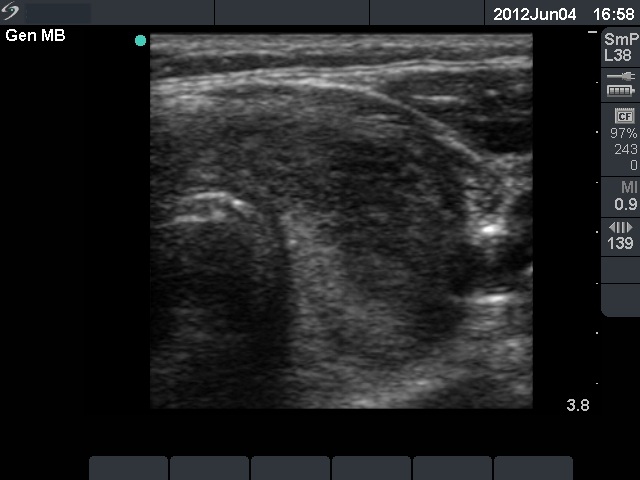

First examination (1st and 2nd rows of images):

Clinical presentation: a 45-year-old man was referred for an evaluation with typical complaints of subacute thyroiditis: fever, pain in the region of the thyroid lasting for 2 months .

Palpation: both thyroids were firm and painful.

Functional state: moderate degree of hyperthyroidism with TSH-level 0.001 mIU/L, FT4 29.1 pM/L. ESR was 70 mm/H while CRP 20.8 mg/L.

Ultrasonography: there were multiple hypoechogenic areas with blurred borders within echonormal background. The vascularization was decreased.

Cytological diagnosis: subacute, granulomatous de Quervain's thyroiditis.

Suggestion: steroid therapy.